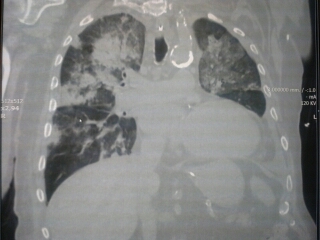

CAP, CURB, PSI, SEPSI, CICCI’ E COCCO’

Tutti infetti e tutti con problemi respiratori. In questo periodo dell’anno è la norma. E in ospedali che traboccano di pazienti e di microbi, bisogna cercare di selezionare bene chi dobbiamo ricoverare e chi possiamo mandare a casa. Arriva Giorgio. Da 4 gg tosse, febbre e dipnea. Ha 75 anni. Obiettivamente non ha un grosso…